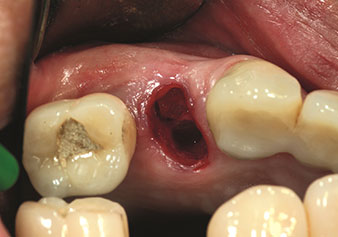

One application, which is often underestimated is the atraumatic extraction of tooth roots or root fragments in the scope of alveolar management. The fine periotomes, which are currently available in two versions (EX1 and EX2 from W&H), can also be used to remove teeth which have previously undergone special endodontic treatment or ankylosed roots with ease. This results in extraction alveoli where both the hard and soft tissue are fully intact as it is generally possible to avoid reflection.

This establishes the optimal basis for subsequent or immediate implant treatment (Figures 1 and 2 included with the kind permission of Dr Torsten Conrad, Bingen a. Rhein).

Photo: © Dr Torsten Conrad (Bingen am Rhein)